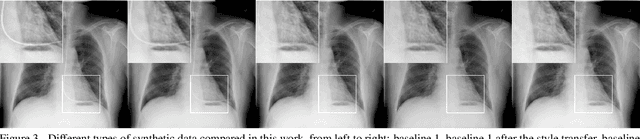

Abstract:Chest X-ray is one of the most widespread examinations of the human body. In interventional radiology, its use is frequently associated with the need to visualize various tube-like objects, such as puncture needles, guiding sheaths, wires, and catheters. Detection and precise localization of these tube-like objects in the X-ray images is, therefore, of utmost value, catalyzing the development of accurate target-specific segmentation algorithms. Similar to the other medical imaging tasks, the manual pixel-wise annotation of the tubes is a resource-consuming process. In this work, we aim to alleviate the lack of the annotated images by using artificial data. Specifically, we present an approach for synthetic data generation of the tube-shaped objects, with a generative adversarial network being regularized with a prior-shape constraint. Our method eliminates the need for paired image--mask data and requires only a weakly-labeled dataset (10--20 images) to reach the accuracy of the fully-supervised models. We report the applicability of the approach for the task of segmenting tubes and catheters in the X-ray images, whereas the results should also hold for the other imaging modalities.